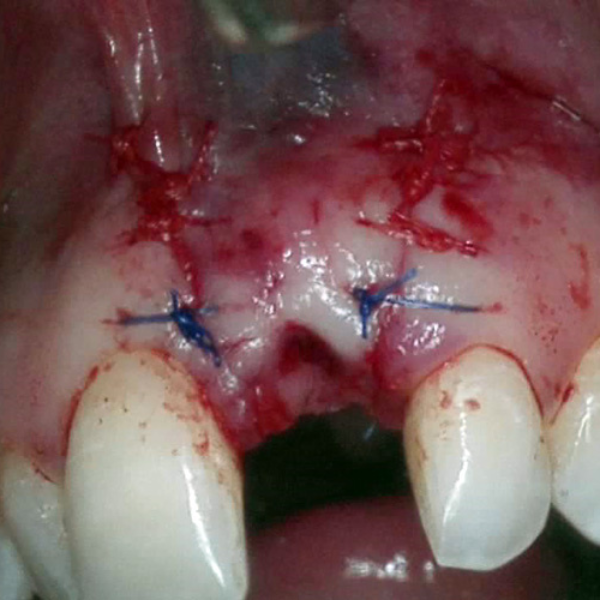

Resorbable Suture Tenting

Pain from a mobile upper right central incisor that had received trauma approximately ten years prior to presentation.